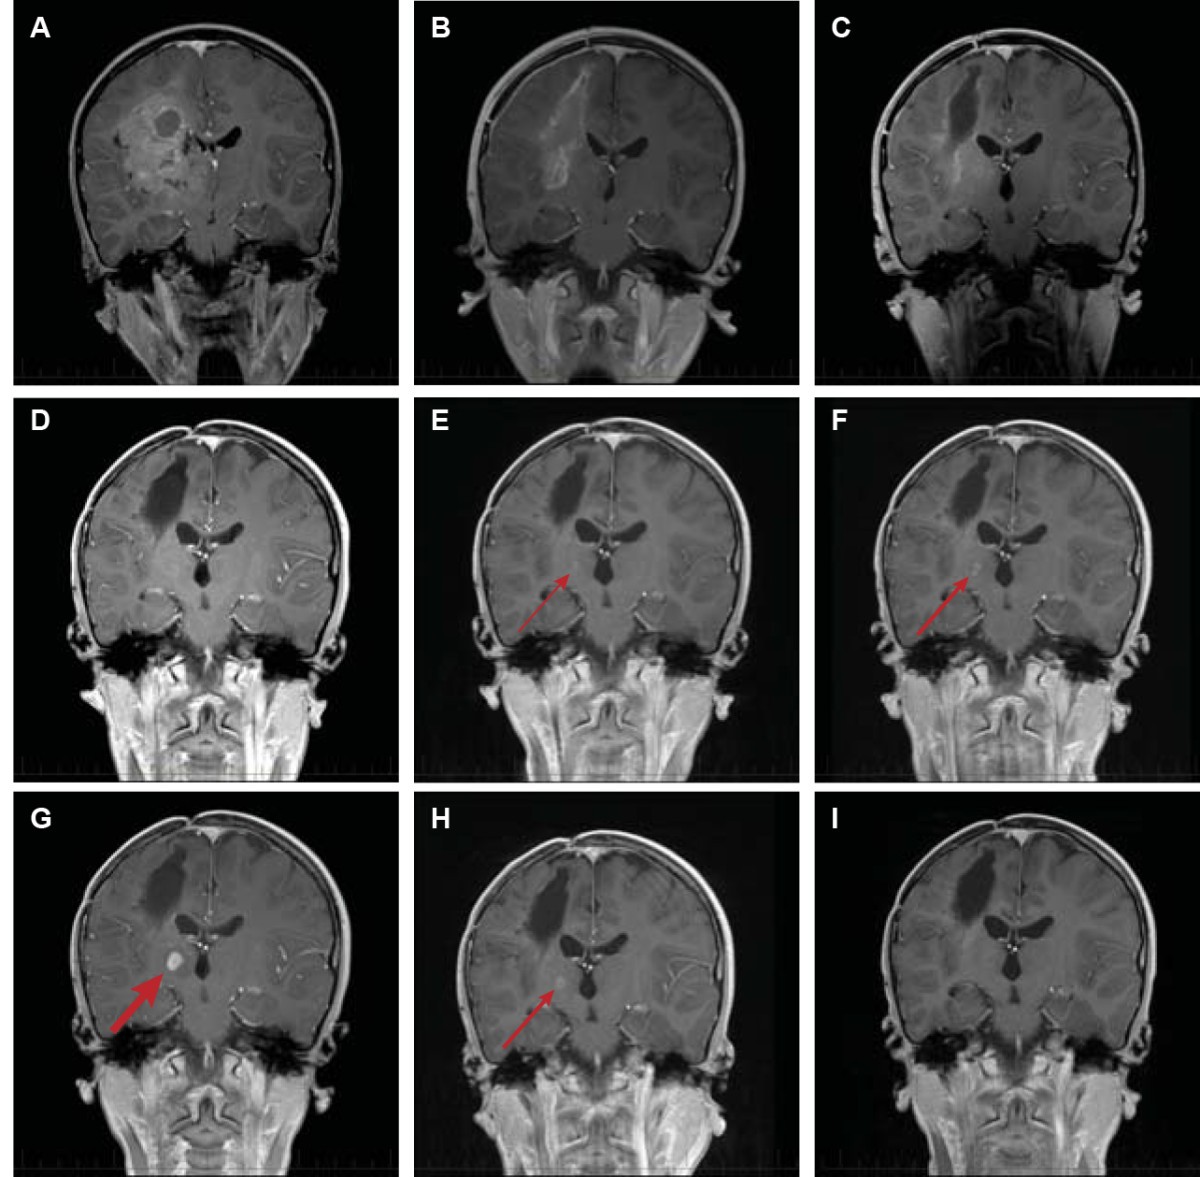

Current treatment options at diagnosis are multimodal and include surgical resection, radiation, and chemotherapy. Concerning medication, 95% received opioids. Mri is used to monitor the tumor.

Mri is used to monitor the tumor. The standard treatment for gbms is surgical resection followed by chemoradiotherapy. Then radiation and chemo follow.